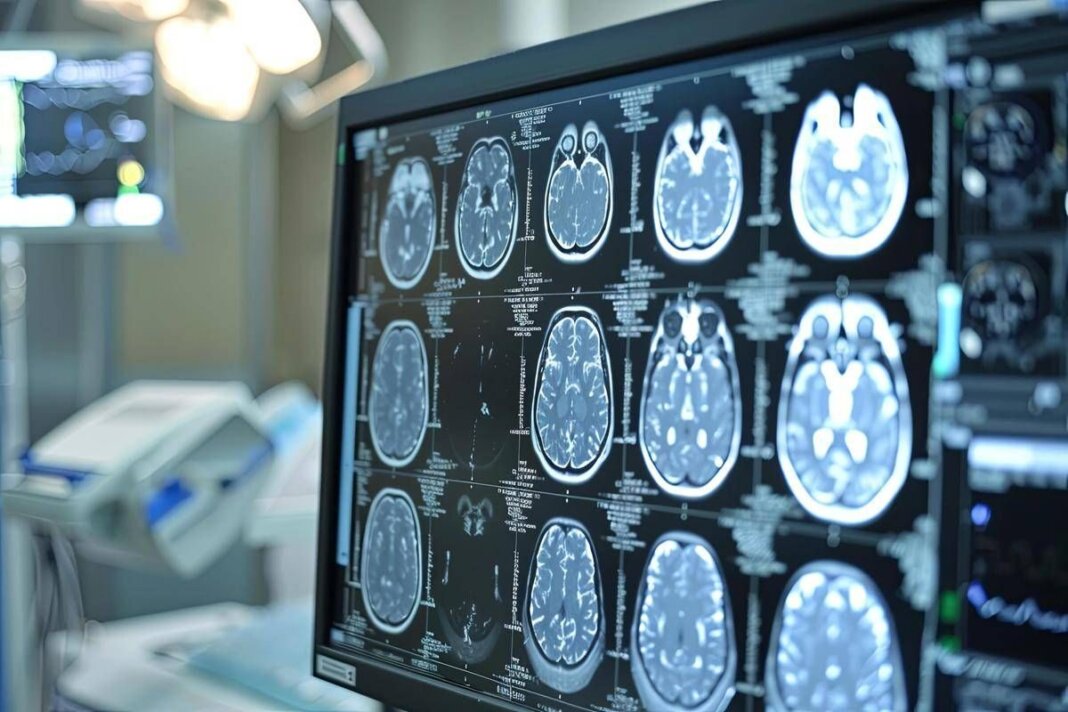

“Sono tumori cerebrali molto complessi e che spesso vengono diagnosticati in età giovanile – afferma Saverio Cinieri, presidente di Fondazione Aiom – Si sviluppano da cellule del cervello chiamate gliali e possono avere una prognosi variabile, ma potenzialmente a lungo termine. La gestione della patologia richiede una stretta collaborazione fra neurochirurgo, radioterapista e oncologo medico. Attraverso il bisturi è possibile rescindere la massa tumorale oppure eseguire una biopsia grazie a nuove e sofisticate tecnologie. La radioterapia permette di ridurre il rischio di recidiva o eliminare quella parte di cancro che non è stato possibile rimuovere chirurgicamente. Viene somministrata insieme alla chemioterapia e le sedute sono di solito diluite nel corso del tempo, per limitare l’impatto degli effetti collaterali. Infine, l’oncologo medico deve scegliere i farmaci da somministrare e deve selezionarli valutando le condizioni cliniche del singolo paziente”.

“Anche per il trattamento dei gliomi, in particolare quelli di basso grado, si può ricorrere all’oncologia di precisione che potrà ridisegnare la pratica clinica nel prossimo futuro – illustra Enrico Franceschi, direttore dell’Oncologia del sistema nervoso all’Irccs Istituto delle scienze neurologiche di Bologna – E’ molto importante verificare la presenza o meno delle mutazioni Idh1 e Idh2. Questi biomarcatori indicano specifiche patologie caratterizzate da una prognosi decisamente più favorevole e maggiore sensibilità dei gliomi alla radio e chemioterapia. Al momento della diagnosi è quindi essenziale l’esecuzione precoce di alcuni test molecolari per identificare al meglio i diversi sottotipi di gliomi. Tra le terapie di nuova generazione vi è anche vorasidenib, un farmaco orale inibitore Idh1 e Idh2 che ha dimostrato di essere un trattamento efficace nel posticipare la radio e chemioterapia nei gliomi di basso grado ed è una rilevante innovazione medico-scientifica”.

“Ancora una volta l’oncologia medica è centrale nella gestione multidisciplinare di neoplasie estremamente complesse ed insidiose – sottolinea Franceschi – Il trattamento dei gliomi inizia nel momento della diagnosi che deve essere sia morfologica che molecolare. Esistono infatti 150 diversi sottotipi di neoplasia cerebrale ed è fondamentale riconoscere fin da subito le caratteristiche del singolo caso per poter così selezionare le terapie più appropriate. Fino a pochi anni fa avevamo a disposizione solo chirurgia, radioterapia e chemioterapia. Ora i farmaci ad azione mirata sono una realtà anche nella cura dei tumori cerebrali che esprimano specifiche alterazioni molecolari”.